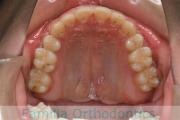

No.19V-044

- 上顎前突

- 13歳

- 女性

- 上:

- 44

- 下:

- 8558

- 主な使用装置:

- FEA

- 治療にかかった費用:

- 85万円

出っ歯を治したいということで小学生の時に来院されました。中学生になるまで経過観察をして、診断、上下左右から小臼歯を抜歯してマルチブラケット法にて治療を行いました。2年強、30回程度の通院が必要でした。

口元の突出感も大きく改善しています。

上顎

下顎

前歯の関係など

上下とも前歯の叢生(でこぼこ、凹凸、ガタガタ)がありましたので、保定をしっかりやらないと後戻りのリスクが出てきます。